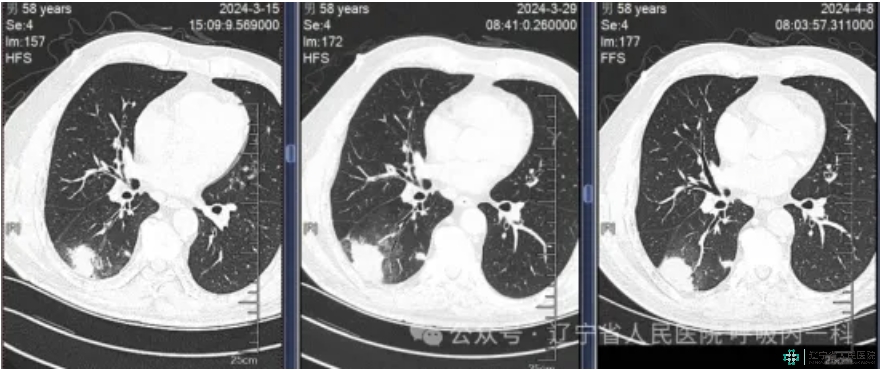

男性患者,58岁,因“咳嗽咳痰伴乏力1周”入院。糖尿病血糖控制不佳。查体无发热,未及确切阳性定位体征。肺CT检查显示右下肺多发团块影。考虑需警惕隐球菌感染。进一步完善相关检查后明确诊断为肺隐球菌病。给予针对性治疗10日后,复查CT发现肺部病灶减轻。